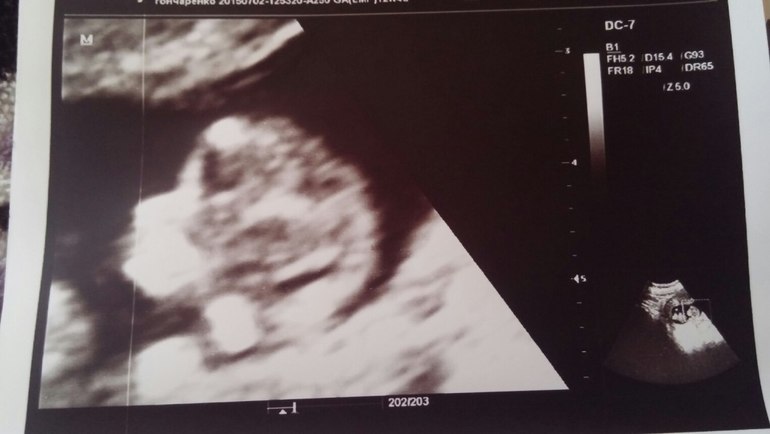

Это профиль)![]()